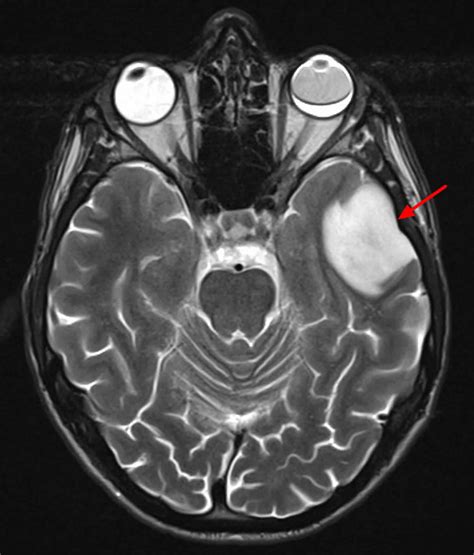

When a radiologist reviews brain imaging, they look for areas that show different signal intensities than the surrounding, healthy brain matter. These differences can be caused by various underlying processes, ranging from inflammation and infection to vascular issues or tumors. Because the causes are so diverse, it is impossible to determine the nature of a lesion based solely on its appearance on a scan; further investigation is almost always required.

• Vascular Issues: Often related to small vessel disease, chronic hypertension, or past mini-strokes (TIAs).

• Autoimmune and Inflammatory Conditions: Diseases like Multiple Sclerosis (MS) frequently cause demyelinating lesions.

• Infections: Abscesses, viral infections (like encephalitis), or fungal infections can create focal areas of inflammation.

• Neoplasms: Both benign (non-cancerous) and malignant (cancerous) tumors can appear as lesions.